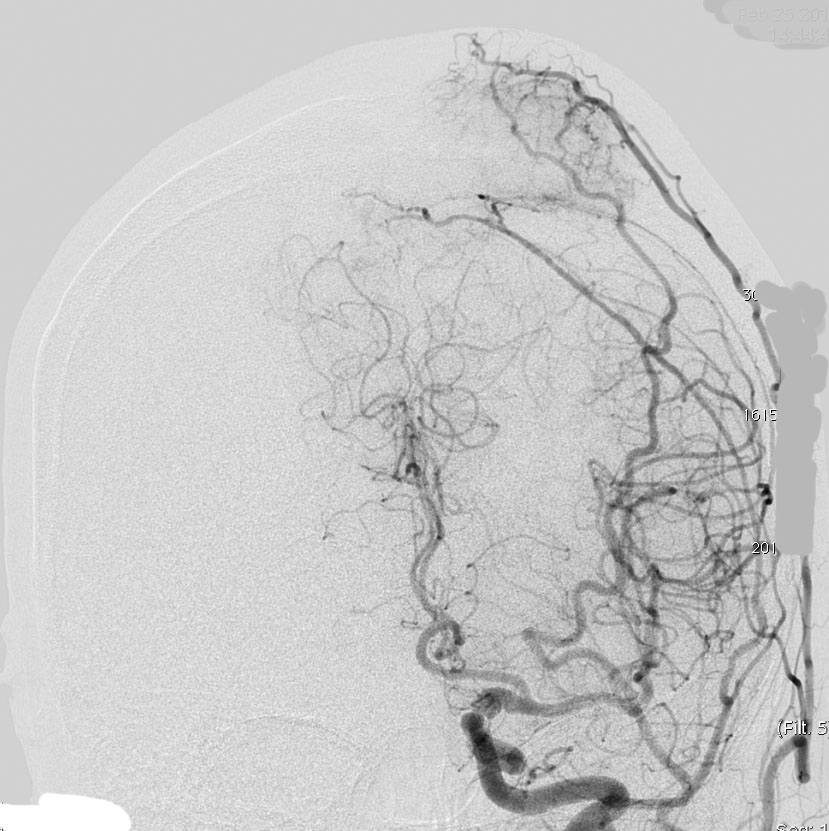

上矢状洞髄膜腫 superior sagittal sinus meningioma

上矢状洞を埋め尽くすように増大して,頭蓋骨浸潤が著しい髄膜腫ですが,ごく軽度の右足脱力以外に何の症状もありません。上矢状洞はゆっくり閉塞すれば,このような頭頂部から後頭部にわたる広範閉塞でも,静脈還流に障害がない場合が多いといえます。大脳の前半部の血流は前頭葉表面の皮質静脈から海綿静脈洞に側副路を形成しています。頭蓋内圧亢進所見もなく,これらはこの髄膜腫がゆっくり増大したということを示唆しています。

手術直後の画像です。全部いっぺんに摘出するのは無理なので,まず前から80%くらいの腫瘍を摘出しました。肥厚した骨はチタンプレートで置き換えてあります。後頭部の上矢状洞内と大脳鎌に少し残りましたが,この6ヶ月後に2回目の開頭術をして全摘出しました。結果的にこの例では,上矢状洞を冠状縫合のあたりから,静脈洞交会まで壁ごと全部摘出しましたが,脳浮腫も何も生じませんでした。腫瘍の両側にある皮質静脈 cortical veinsを損傷しないことが肝要です。

右の病理像は,頭蓋骨浸潤している部分 ですが,骨破壊は良性髄膜腫に特徴的な骨内浸潤像です。この骨浸潤像は悪性像とはいえません。MIB-1は高いところで8%、低いところで3%程度です。